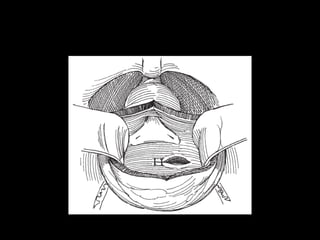

Fractura de uretra posterior

90% Causa de Fracturas Pelvianas

Accidentes de trafico

Caidas de grandes alturas

Cuadro clinico

• Triada

Hematuria + Uretrorragia + Retención aguda

Hematoma perianal

Prostata elevada